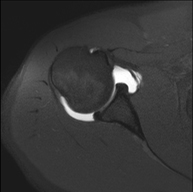

- Shoulder MRI

Examination to study injuries to tendons, muscles and joints. Its main use is to diagnose injuries to the rotator cuff tendons. It lasts approximately 20 minutes. It is a radiation-free procedure.